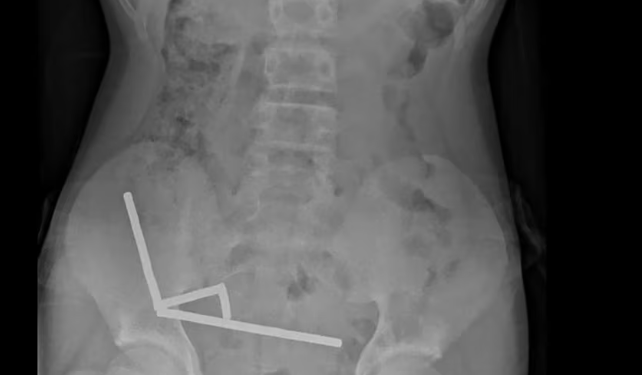

Skanimet treguan se magnetët ishin grumbulluar në anën e djathtë të poshtme të barkut, duke tërhequr pjesë të ndryshme të zorrës me forcën e tyre magnetike. Disa imazhe mjekësore ishin shtrembëruar për shkak të magnetëve.

Mjekët kryen një ndërhyrje kirurgjikale eksploruese dhe zbuluan se magnetët kishin shkaktuar nekrozë nga presioni në disa pjesë të zorrës dhe të zorrës së trashë. Ata arritën t’i hiqnin magnetët me sukses, por djali humbi një pjesë të zorrës. Ai qëndroi tetë ditë në spital për rikuperim para se të dilte.